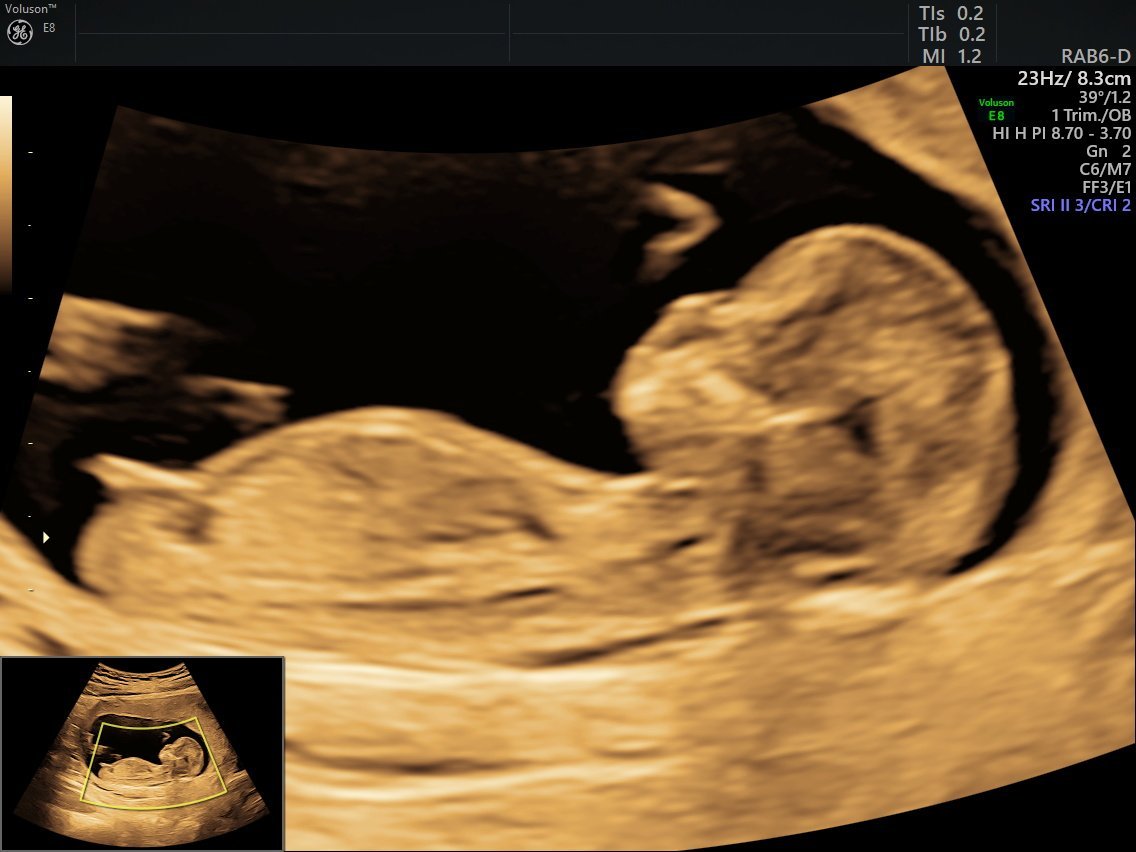

Happyday ами тук пак ли на момиче ти прилича 🤔 Ох и на момиченце ще се радвам, ама името не знам какво ще го правим, таткото предлага да обърнем същото име в женски вариант, ако е момиче, ама си ми харесва повече за момченце името 😅

Лотос пак прилича на момиченце,пак е сякаш успоредна костта,ама все пак не гарантирам нищо, мислете си имена и за двата пола да си имате приготвени 🙂

Galq В 10та е рано за тази теория с костта, уж не е валидна,но ако трябва да предполагам ще кажа момче,заради топченцето. Ще кажеш после какво е излезнало.